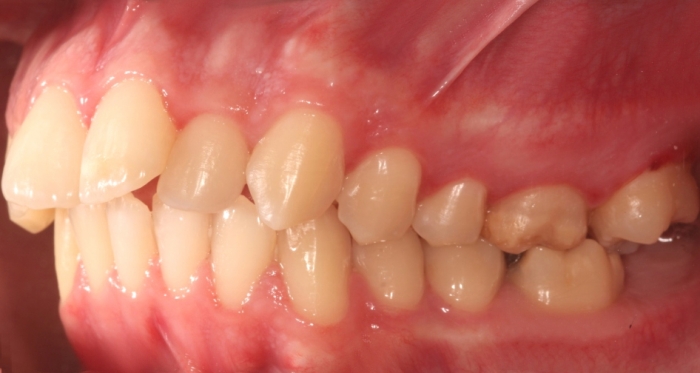

Mordida inicial - Clínica Cliniface

Mordida inicial